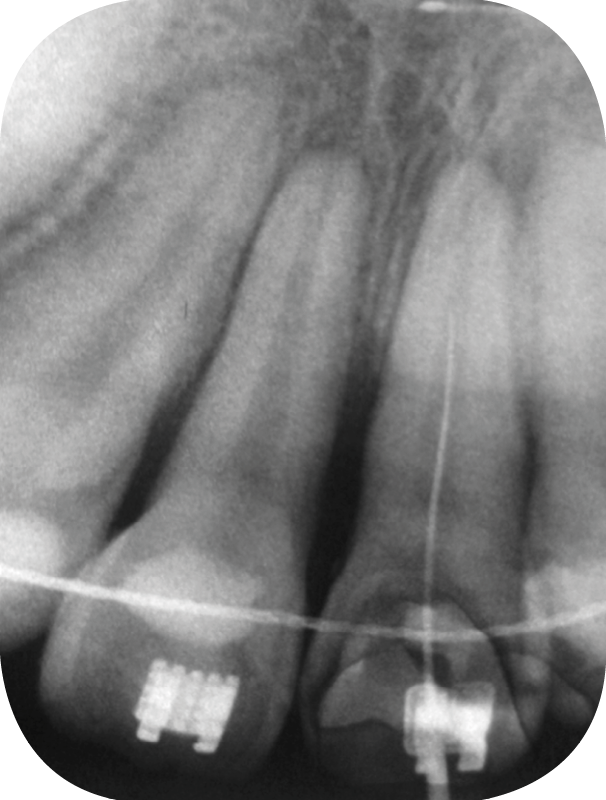

1. Une semaine après la réimplantation. Désinfection canalaire et obturation au Ca(OH)2 de la 21.